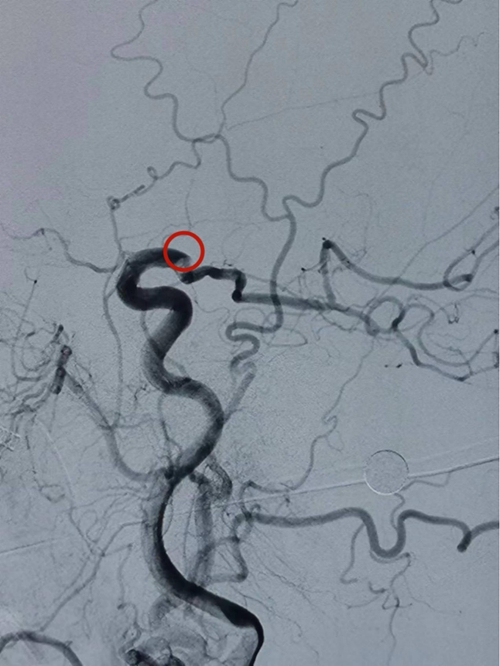

△造影显示左侧颈内动脉远端闭塞

在溶栓进行的同时,“取栓小组”在麻醉科、介入导管室的全力配合下,迅速完成了取栓的术前准备工作,随即对患者进行了“桥接”血管内介入治疗。根据术中造影显示,考虑左侧颈内动脉远端闭塞。